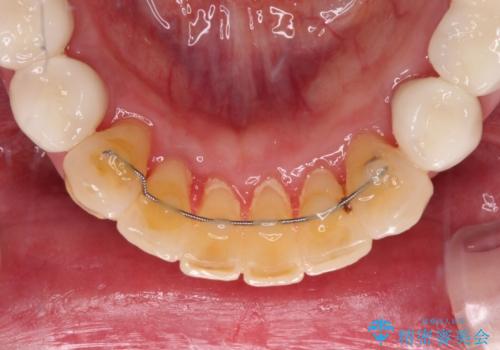

歯肉の状態が落ち着いた後に下顎の矯正治療を行い、その後補綴治療を行うこととしました。

油断をするとすぐに汚れが溜まって歯肉が腫れてきてしまうため、今後も定期的なメインテナンスが重要となります。